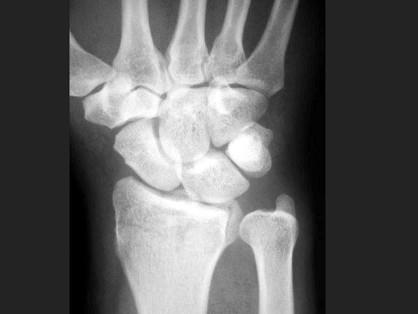

问题 男,22岁,滑冰时摔倒右手撑地时受伤,结合CR片,最可能的诊断是?(?)

选项 A.柯莱斯骨折 B.蒙泰贾骨折 C.加莱阿齐骨折 D.桡骨远端骨折 E.反柯莱斯骨折

答案 D